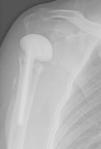

DiagnosisProximal humeral osteomyelitis with stage IV B Cierny–Mader,4 due to coagulase-negative Staphylococcus. Culture antibiogram indicated susceptibility to penicillin, cephotaxime, erythromycin, tetracycline, levofloxacin, and vancomycin cotrimoxazole. Scintigraphic uptake (Fig. 2).